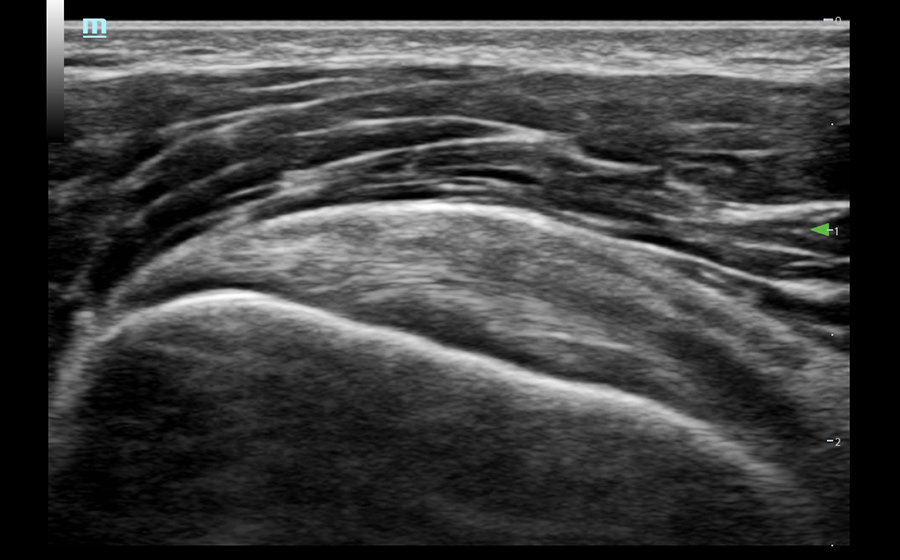

Obrazy kliniczne